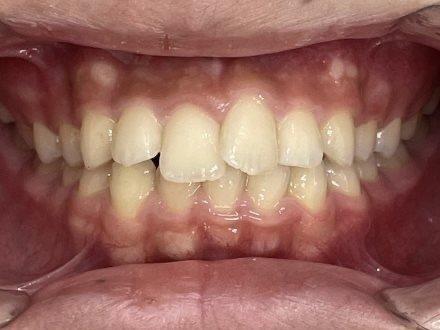

Before

After

矯正の種類 / invisalign GO

年齢・性別 / 30代男性

主訴  /  下の歯の叢生、オーバージェット、交叉咬合

治療期間 / 12ヶ月

費用 / 簡易検査 5,000円(税別) 精密検査 30,000円(税別)

両額マウスピース 450,000円(税別) 両額リテイナー料 40,000円(税別)

※マウスピース交換時別途調節料5,000円(税別)

副作用 / 口内炎・歯の移動に伴う痛み・知覚過敏 ※数日で収まる場合が多いです

リスク / 後戻り防止の為、夜のみマウスピースで保定を指示